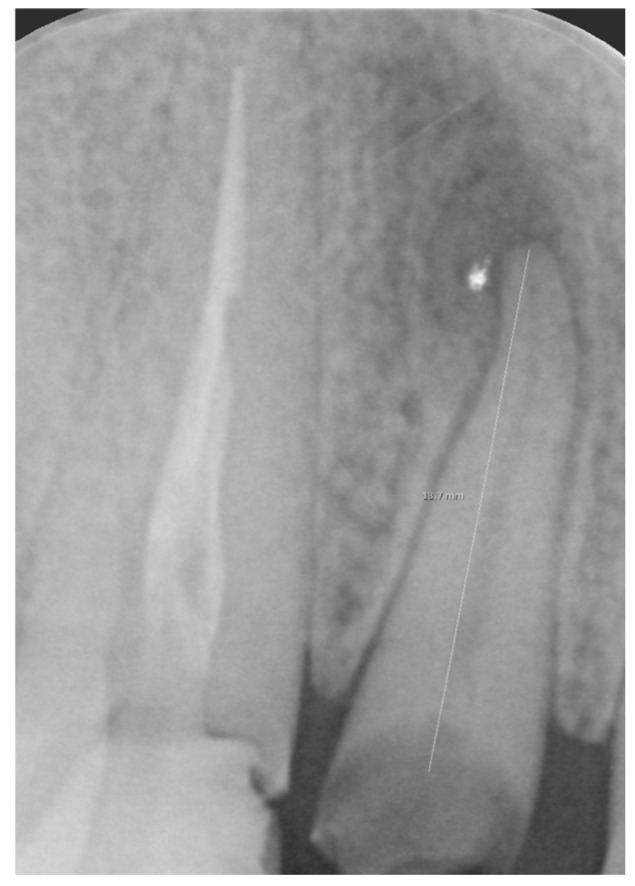

背景。正畸挤出(OE),或强制出牙,是一种保守的技术,用于恢复受冠状骨折,创伤性侵入或严重龋齿影响的牙齿。它包括施加轻的,连续的力量来诱导牙齿垂直运动,通过牙周韧带刺激促进组织重塑。材料与方法。这篇叙述性综述包括研究OE作为治疗深部或龈下龋齿病变、创伤性牙齿损伤(如侵入或骨折)或种植体发育过程中牙槽嵴增大的治疗方法。OE通常使用固定设备进行,例如直丝系统,或者在特定情况下使用透明对准器。根据临床情况,每颗牙齿施加30至100克的力。在一些方案中,OE与纤维切开术相结合以减少牙龈和骨迁移。结果。研究表明OE导致显著的垂直运动,增加颊骨高度和近端间隔。它增加了目标部位的骨体积,使其在种植体部位发育中具有价值。与外科牙冠延长术相比,OE能更好地保护牙周组织,改善美观。结论。在这篇叙述性综述中,我们分析了OE如何有效地治疗创伤性侵入和牙周部位受损,特别是当与早期牙髓治疗相结合时。它减少了强直和牙根吸收的风险,同时避免了移植等侵入性手术。尽管透明对准器可能会限制牙齿轴向运动,但OE仍然是修复和种植牙科的微创,成本效益高的替代方法。

Background. Orthodontic extrusion (OE), or forced eruption, is a conservative technique used to recover teeth affected by coronal fractures, traumatic intrusions, or severe caries. It involves applying light, continuous forces to induce vertical tooth movement, promoting tissue remodeling through periodontal ligament stimulation. Materials and Methods. This narrative review included studies investigating OE as a therapeutic approach for the management of deep or subgingival carious lesions, traumatic dental injuries (such as intrusion or fracture), or for alveolar ridge augmentation in implant site development. OE is typically performed using fixed appliances such as the straight-wire system or, in selected cases, clear aligners. Forces between 30 and 100 g per tooth are applied, depending on the clinical situation. In some protocols, OE is combined with fiberotomy to minimize gingival and bone migration. Results. Studies show that OE leads to significant vertical movement and increases in buccal bone height and interproximal septa. It enhances bone volume in targeted sites, making it valuable in implant site development. Compared to surgical crown lengthening, OE better preserves periodontal tissues and improves esthetics. Conclusions. In this narrative review is analized how OE is effective for managing traumatic intrusions and compromised periodontal sites, particularly when paired with early endodontic treatment. It reduces the risks of ankylosis and root resorption while avoiding invasive procedures like grafting. Although clear aligners may limit axial tooth movement, OE remains a minimally invasive, cost-effective alternative in both restorative and implant dentistry.